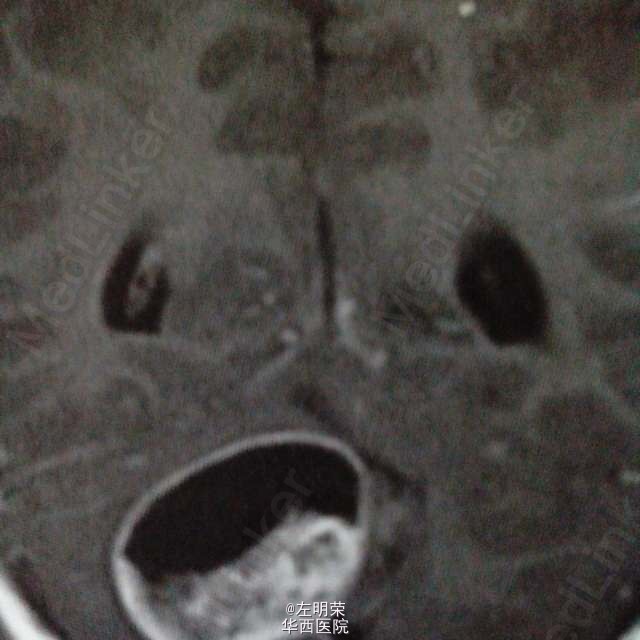

髓母细胞瘤

6岁小儿,主诉间断性头痛伴恶心,呕吐6天。影像特点:右侧小脑半球可见明显强化的囊实性占位,囊内可见出血后形成的液平,瘤旁轻微水肿。考虑星形细胞瘤,髓母细胞瘤,室管膜瘤可能。行手术切除治疗,见囊实性肿块,囊内坏死出血,肿瘤血供丰富,边界不清,近全切。病理结果:髓母细胞瘤